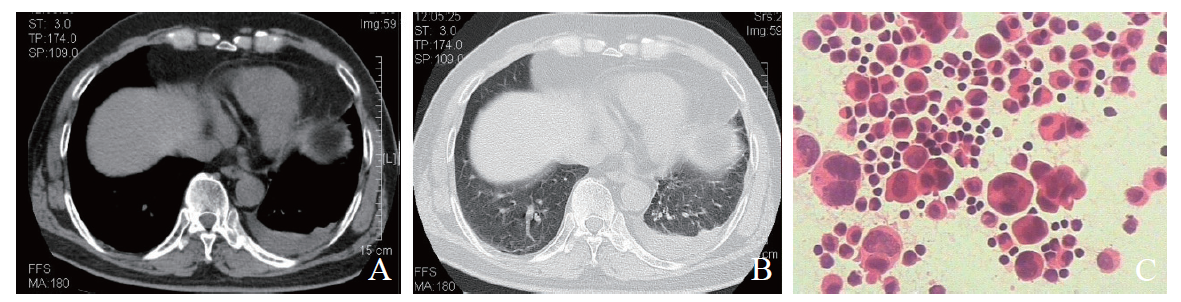

例3 患者女,59岁。因头晕6个月,头痛10余日于2017年5月13日在我院神经内科就诊。6个月余前患者无明显诱因出现发作性眩晕,体位变化时明显,10余日前出现头痛、头晕伴恶心、呕吐胃内容物多次,偶有喷射样呕吐,头痛较剧烈,以前额为主,休息后可缓解,头痛时伴视物模糊、眼前发黑感,9 d前曾出现头痛时意识障碍、大小便失禁并出现发热,体温最高38℃,当地医院查头颅MRI/磁共振血管成像(MRA)未见明显异常,胸部X线片示左肺下叶感染,予抗感染、止痛、退热等治疗后未再发热,仍反复头痛、头晕,伴恶心、呕吐,体质量近1月下降约3 kg。既往有乙型肝炎史,个人史无特殊。入院体格检查:体温:36.8℃,脉搏82次/分,呼吸18次/分,血压142/78 mm Hg。神清,对答切题,双侧瞳孔等大、等圆,直径约3 mm,远视力变差,对光反射灵敏,可见水平眼震,伸舌居中,鼻唇沟无变浅,躯干四肢深浅感觉无明显异常,四肢肌力、肌张力正常,颈项强直,克尼格征(+),双侧巴宾斯基征可疑阳性。入院后完善检查,血常规示:血红蛋白127 g/L,白细胞9.18×109/L,血小板30×109/L;脑脊液涂片示隐球菌1 982 /ml;脑脊液生化常规示糖 2.59 mmol/L,氯115.4 mmol/L,脑脊液蛋白0.62 g/L,白细胞计数14×106/L,无色、透明、清亮、无薄膜形成,球蛋白定性(+),红细胞24×106/L。10月18日胸部CT示:①左肺下叶基底段病变,考虑真菌感染;②双肺少许炎症,左肺下叶基底段见多发斑片状、结节状实变影,边界不清,内部密度不均,内可见结节状高密度阴影,病灶较前稍减少(图3A、B),余双肺见少许斑片状稍高密度影。肺部病灶抗感染治疗后于11月10日复查CT,结果示较前进展,遂完善纤支镜检查,12月14日BAL涂片及液基细胞学示较多泡沫样细胞及少量上皮细胞、淋巴细胞,未见确切癌细胞(图3C)。特殊染色结果:PAS(-),抗酸染色(-),六氨银(-)。长期使用伏立康唑联合氟胞嘧啶抗感染治疗后复查CT好转。

图3 例3肺隐球菌感染患者的胸部CT及BAL涂片结果

A:胸部CT纵隔窗;B:胸部CT肺窗;C:BAL涂片(HE染色,×400)